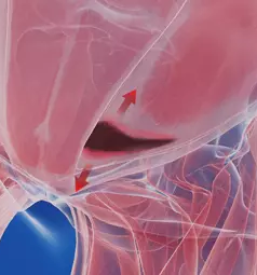

Športnikova kila je izraz za bolečinski sindrom v dimljah, ki je precej kompleksen tako glede diagnostike, kot samega zdravljenja.

Razlogov za bolečino v dimljah je veliko, lahko gre za pravo kilo, ki se vidi kot izboklina iz trebuha ob napenjanju, pogosti vzroki so lahko okvare hrbtenice, pri katerih bolečina pasasto seva v dimlja, možni pa so tudi razni urološki vzroki.